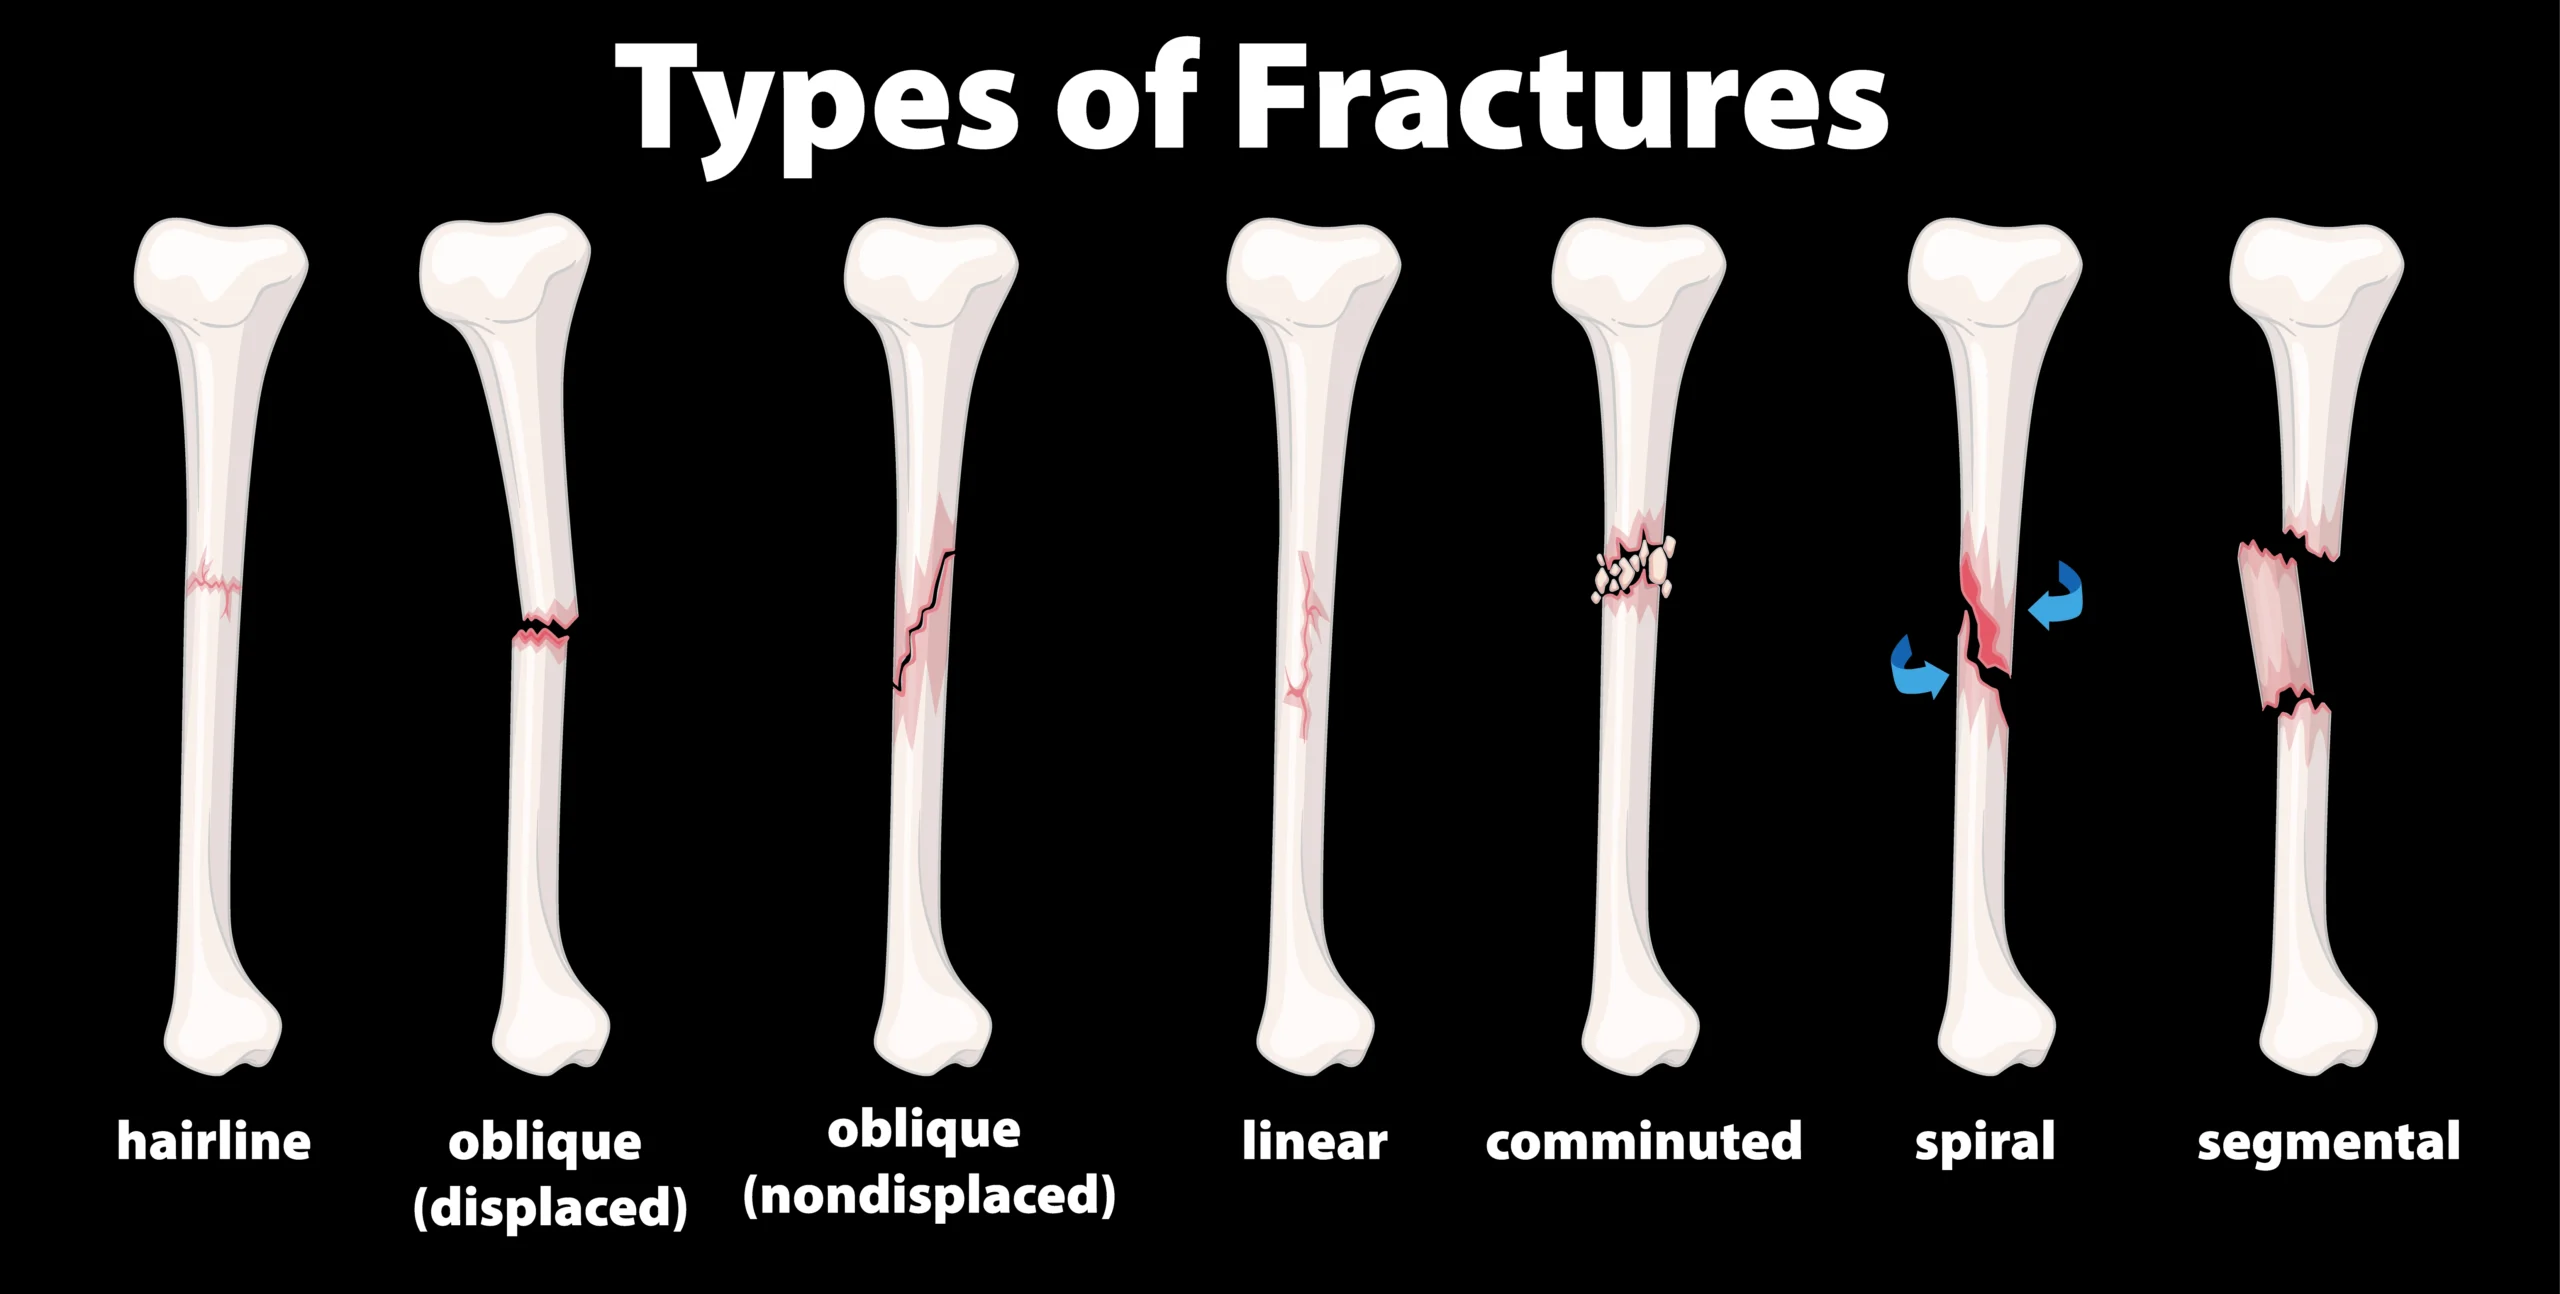

Types of Bone Fractures

Closed Fracture

Bone is broken, but the skin is not broken.

Open Fracture

Bone breaks and skin opens. High infection risk exists.

Displaced Fracture

Bone ends move apart.Alignment is abnormal.

Non-Displaced Fracture

The bone breaks, yet it is not dislocated.

Comminuted Fracture

Bone breaks into various fragments.

Impacted Bone Fractures

In impacted bone fractures, fragments of the bones are beaten into one another.